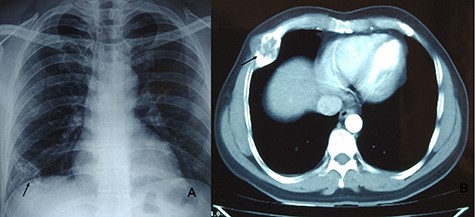

A 43-year-male presented with complain of incidentally detected swelling on the right lateral chest wall of 6-month duration not associated with pain or tenderness. He denied any history of trauma or prior chest surgery, and his past medical history was unremarkable. It was slowly increasing in size. A physical examination revealed a palpable non-tender mass of fifth rib on anterolateral wall of the right chest. His all routine laboratory test results were within normal range. Chest radiograph performed showed lytic lesion of right fifth rib (Fig. 3A). CT chest revealed 40 × 36 × 60 mm well-defined large hypodense cystic lesion of the fifth rib involving anterolateral part (Fig. 3B). Fine needle aspiration cytology was inconclusive. A right anterolateral thoracotomy was done and the right fifth rib was excised. The mass was resected totally along with the adjacent parietal pleura and normal rib segment (Fig. 4A). The chest was closed primarily and did not require any reconstruction. The cut section of specimen revealed gelatinous material covered with thin bony shell. Histopathology confirmed the mass to be enchondroma (Fig. 4B). His post-operative course was uneventful and discharged on 3rd post-operative day without any complaints. After 3 years of follow-up, he is doing well without any recurrence.

CXR showing lytic lesion of right fifth rib (A). CT chest showing well-defined large hypodense cystic lesion of the fifth rib involving anterolateral part (B).